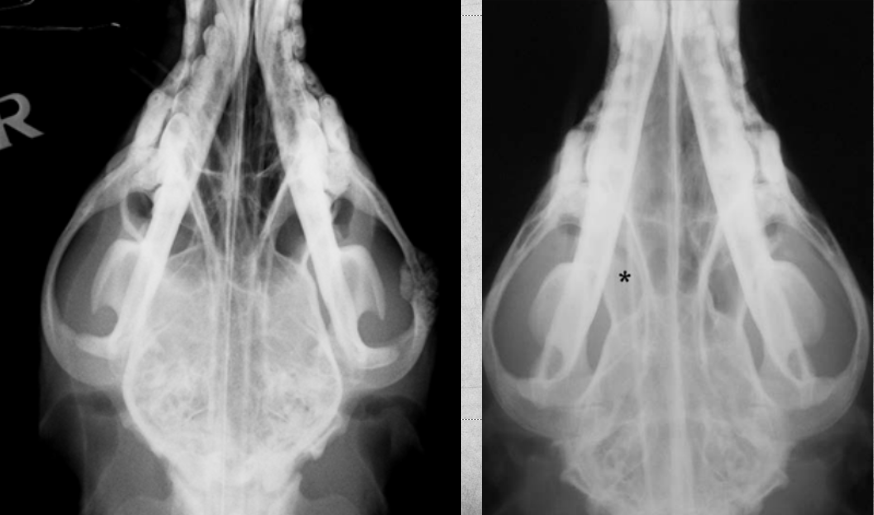

A

left zygomatic arch neoplasia in left image

asterisk marks soft tissue neoplasia in left side image. note the difference in density of that space.